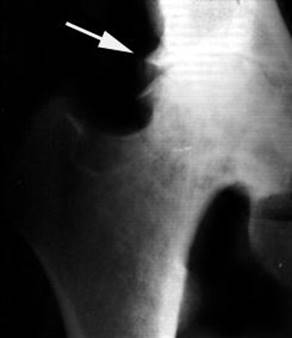

Рентгенодиагностика остеоартроза

Рентгенологическая семиотика остеоартроза складывается из признаков, отражающих дистрофические изменения в суставных хрящах (сужение суставной щели) и в костной ткани (уплощение и деформация суставных поверхностей, кистевидные образования), нестабильность суставов (подвывихи, искривления оси конечностей), реактивные компенсаторно-приспособительные процессы (краевые костные разрастания, субхондральный остеосклероз).

Ранним рентгенологическим симптомом являются краевые костные разрастания — остеофиты — следствие активной пролиферации периферических отделов суставного хряща. Они проявляются вначале заострением краев суставных поверхностей, а затем, нарастая, образуют массивные костные шипы и губы. Краевые остеофиты, как правило, раньше обнаруживаются со стороны суставных впадин.

Сужение суставной щели свидетельствует о значительных изменениях суставных хрящей. Суставная щель может стать клиновидной, суживаясь с одной стороны и нередко расширяясь при этом с противоположной, что указывает на недостаточность связочного аппарата и нестабильность сустава.

При остеоартрозе утрачивается амортизационная функция суставных хрящей, предохраняющих костную ткань от механических перегрузок. Как компенсация развивается остеосклероз субхондральной губчатой кости . Особенно он выражен при коксартрозе в крыше вертлужной впадины, распространяясь иногда почти на все тело подвздошной кости. Однако рано или поздно этот механизм компенсации становится недостаточным. Механические силы, передающиеся непосредственно с одной суставной поверхности на другую, вызывают атрофию от давления их наиболее нагружаемых участков и прежде всего центральных отделов суставных головок. Вследствие этого они уплощаются и одновременно расширяются.

В России распространена рентгенологическая классификация остеоартроза по стадиям развития, разработанная Н. С. Коссинской:

¨ Остеоартроз в I стадии характеризуется главным образом краевыми костными разрастаниями при незначительном сужении суставной щели;

¨ Во II стадии она сужена более отчетливо, возникает субхондральный остеосклероз ;

¨ Резкое сужение суставной щели в III стадии остеоартроза сопровождается уплощением суставных поверхностей и развитием кистовидных образований ;